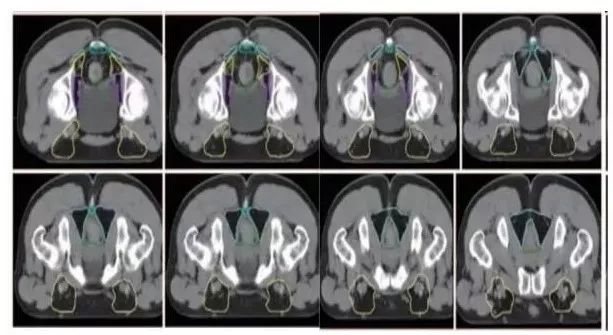

a. 骶前区:骶骨前方区域,包括腹部骶前区⁃PS S (青色) 和盆腔骶前区⁃PS (淡蓝色)(2B 级证据);

b. 直肠系膜区:由全部直肠系膜区以及直肠系膜筋膜组成⁃M(深绿) ;

c. 髂内淋巴引流区⁃LLN P (黄色);

d. 闭孔淋巴引流区⁃LLN A (紫色);

e. 髂外淋巴引流区⁃EI (灰白色);

f. 腹股沟淋巴引流区⁃IN (黄褐色);

g. 坐骨直肠窝⁃IRF (天蓝色);

h. 肛门括约肌复合体⁃SC (桔色)

(b⁃h:1 级证据)。

高危淋巴结引流区及高危复发区边界定义及图谱(CT层厚0.5cm,俯卧位)

勾画图谱